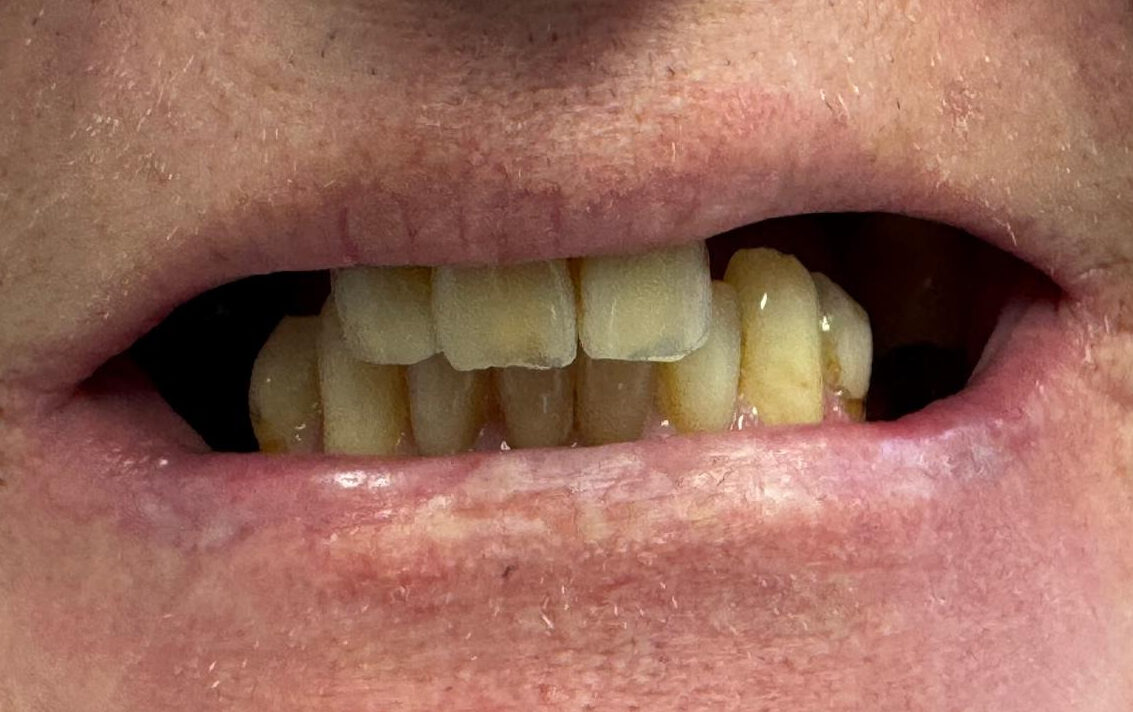

Full Arch on 6 implants

Upper arch (All on XI)

Before

After